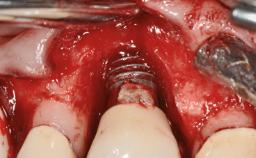

This case describes the ongoing management of a 64-year-old healthy, non-smoking female patient with erosive oral lichen planus (OLP) affecting the gingivae and the buccal and lingual mucosa. The peri-implant mucosa was also affected subsequent to implant placement. The patient had osseointegrated implants (four in the maxilla, four in the mandible) placed following extraction of hopeless teeth and a healing period. The patient had a history of OLP prior to implant placement and had been referred to an oral-medicine specialist for definitive diagnosis and treatment. She exhibited generalized oral mucosal involvement. Following a clinical assessment, biopsy, and blood tests, she was treated with topical corticosteroids. Systemic prednisolone was reserved for severe flare-ups. Amphotericin lozenges were used in combination with corticosteroid treatment to prevent the development of oral candidiasis.